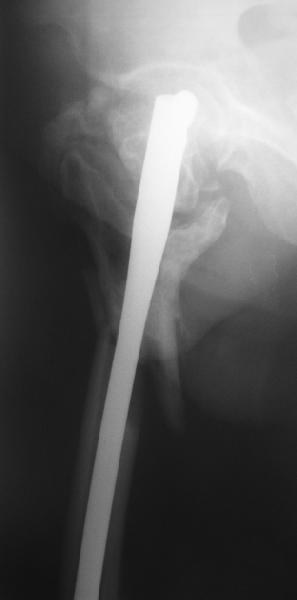

Уважаемые коллеги, помогите определиться с тактикой лечения. Больная, 62 года,жалуется на боли,неопорность левой ноги. Ходит с помощью костылей, укорочение ноги 3 см. Два года назад была оперирована кокой-то накостной пластиной, пластину удалили 4 мес назад. Вопрос такой: предлагать эндопротезирование или делать МОС (что-то по типу стержня Gamma)?За качество снимков извините, по данным МРТ - головка живая

На прошлой неделе оперировали похожего пациента. 2 года после неудачного остеосинтеза PFN в другом регионе. После удаления остатков железа выявилось несращение вертельной области.

В такой ситуации важно устранить варусную деформацию. При использовании гвоздя это непросто. Поэтому в число рассматриваемых

вариантов стоило бы включить вальгизирующую остеотомию с фиксацией 130-градусной клинковой пластиной или DHS.

Если есть сильное желание фиксировать все-таки гвоздем, советовал бы ввести мощный "джойстик" параллельно оси шейки бедра близко к ее задней стенке, сделать поперечную межвертельную остеотомию и использовать дистрактор таз-бедро.

Поскольку в нашем случае выявилась подвижность, мы наложили дистрактор таз-бедро на 3 дня, и сделали остеосинтез гаммой без остеотомии. То, что произошла "корригирующая остеоклазия" в подвертельной области, выявили после введения гвоздя. Пациент уже уехал домой, будем наблюдать.